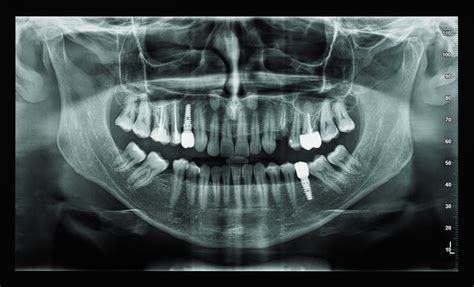

- Planificación de Implantes Dentales

Clínica Velázquez está especializada en todo tipo de tratamientos dentales. Disponen de equipo para hacer tac dental (tac 3d) para tratamientos de implantes dentales, extracción de muelas de juicio, etc. Tac rápido y con poca radiación.

Su equipo de radiografía dental Sirona es uno de los más avanzados en el mercado. Técnicamente, el emisor de luz de Tac dental es un CBCT (Cone Beam Computed Tomography) Tomografía Computarizada de Haz Cónico, que se diferencia del TAC en que estos equipos emiten en forma cónica y los TAC antiguos en forma espiral.

El software de su equipo tiene el sistema MARS (Secuencia de reducción de artefactos metálicos). Es un algoritmo que elimina los artefactos que se producen en las imágenes cuando hay metales (implantes dentales, empastes metálicos, coronas, etc).